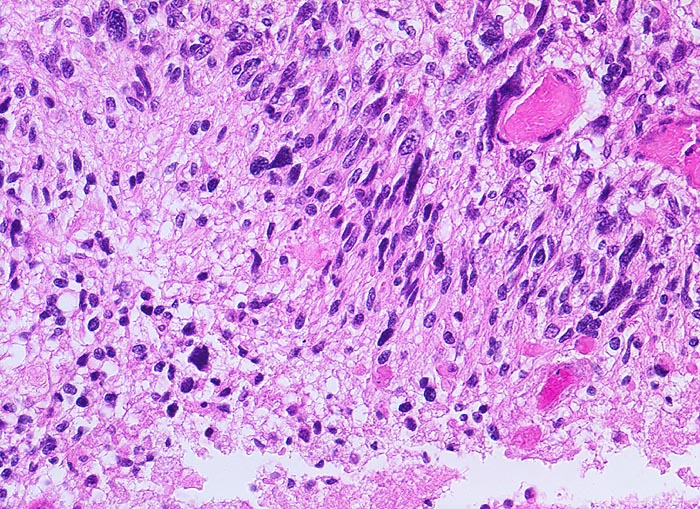

Glioblastoma multiforme WHO Grad IV

Das zytologische Bild gleicht einem hochmalignen Sarkom. Die Tumorzellen sind oft in mehreren Reihen um eine Kapillarachse herum angeordnet. Das Spektrum reicht von kleinen lymphozytenähnlichen Zellen bis zu grossen zytoplasmareichen und mehrkernigen Zellen. Das Kernchromatin ist grob retikulär und die Kerne sind embryonenartig gebuchtet. Mitosen sind oft anzutreffen. Das Zytoplasma kann degenerativ bedingte Vakuolen enthalten. Den Hintergrund bildet ein Gemisch aus fibrillärer Matrix, Blut, Detritus und Kalkpartikeln.